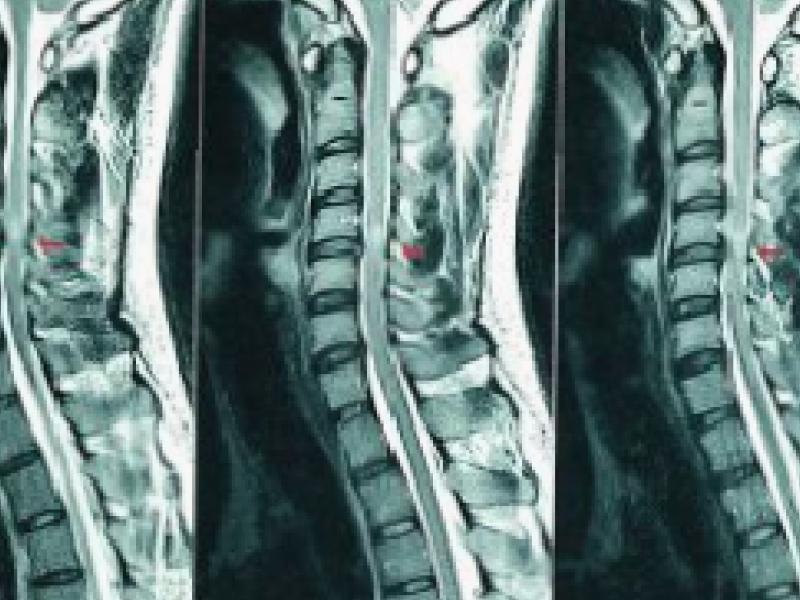

The diagnosis is made by the patient’s complaints, examination and imaging. We use the Modified Japanese Orthopedic Association Scale as an international standard for assessing the severity of spinal cord injury. With the scale, numbness in the arms and legs, weakness and coordination problems, bladder

and bowel problems, fine motor skills of the hands and balance problems are evaluated. MRI is used to evaluate the structure of the spinal cord.